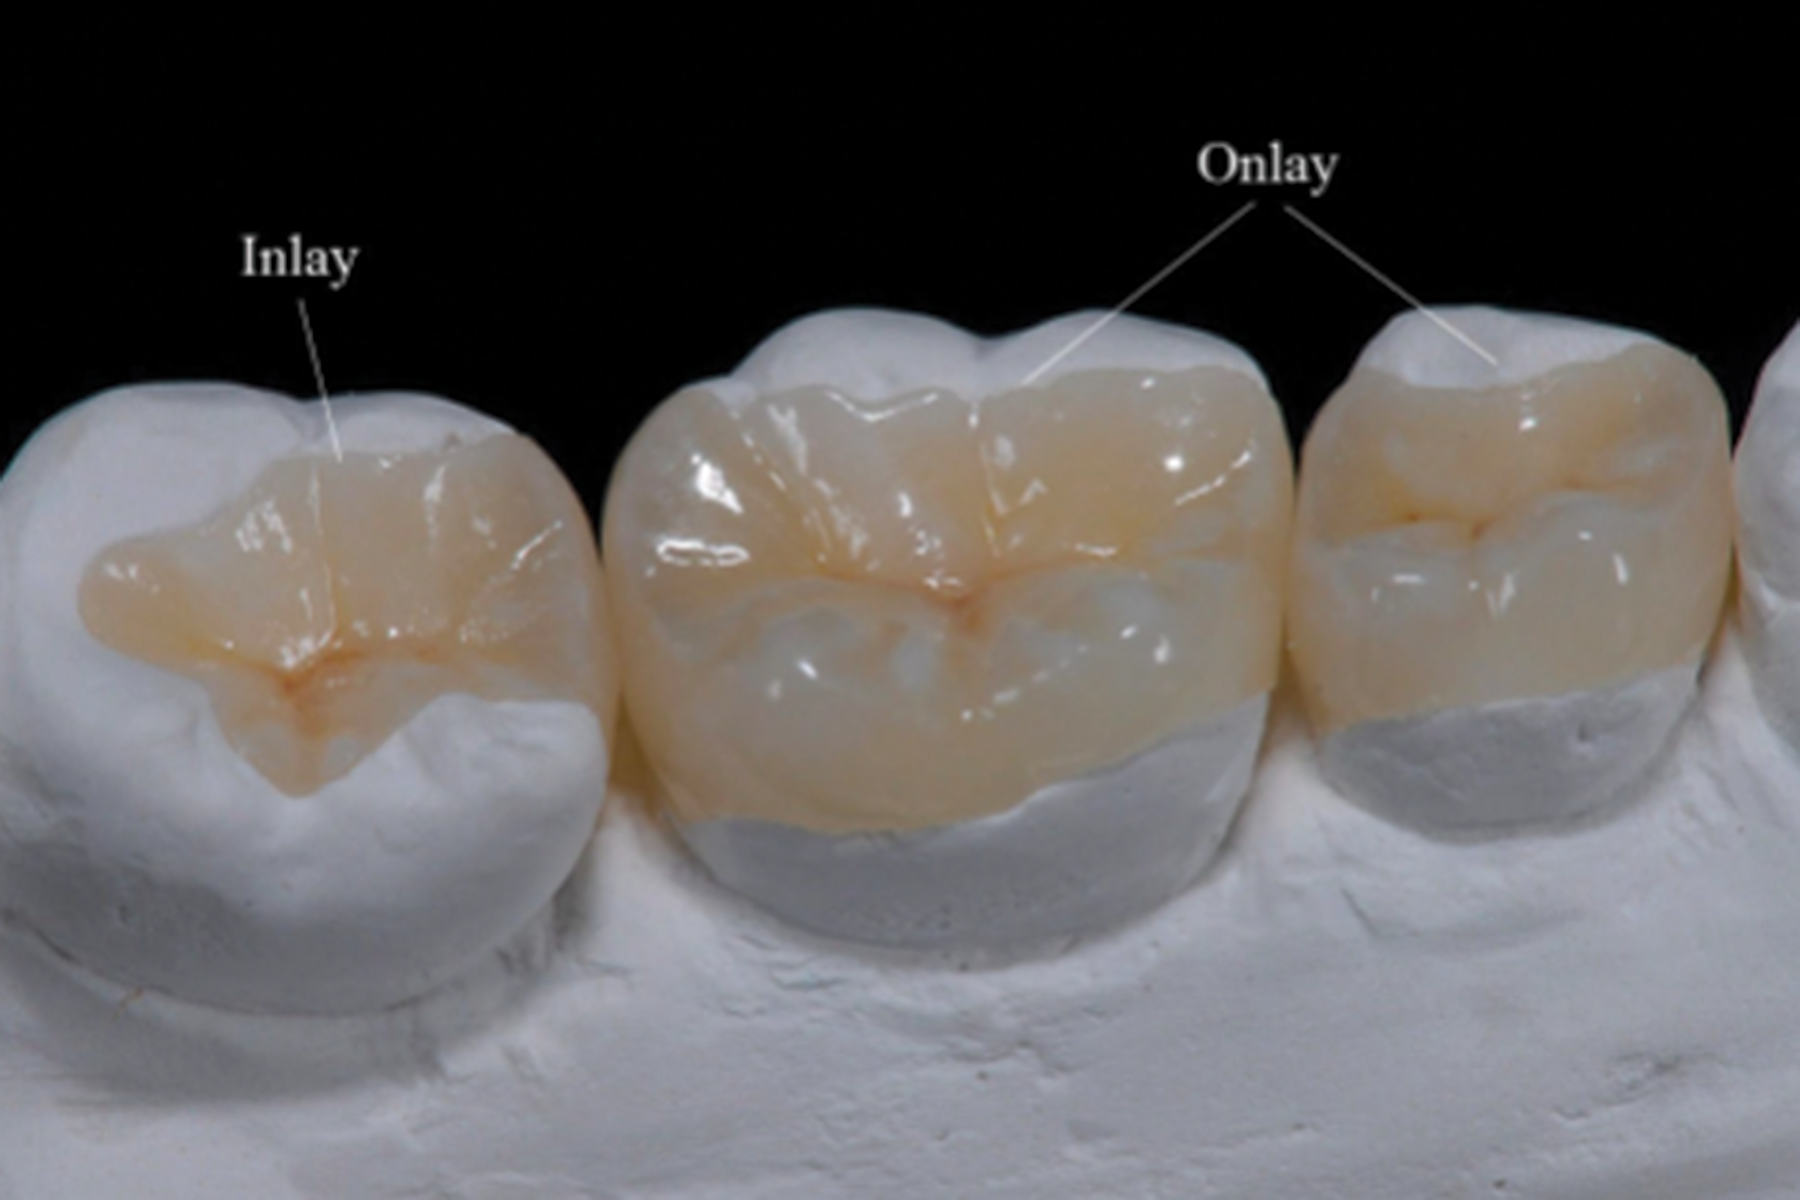

Inlays & Onlays

Une technique moderne d’obturation, les inlays et les onlays sont des alternatives aux plombages ou aux résines. La différence avec le plombage c’est que ces prothèses sont faites par un prothésiste dentaire dans un laboratoire et non par le dentiste sur place au centre.

Inlay – Soins dentaires intérieurs efficaces

Onlay – Soins dentaires extérieurs efficaces